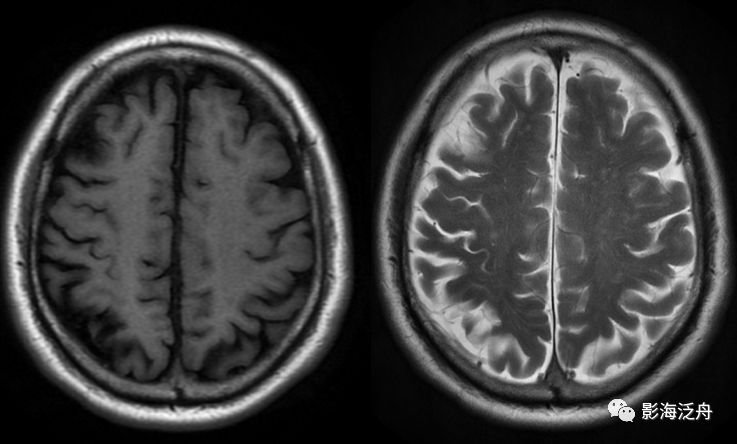

小结:通过上述三个病例,不难发现在颅脑MR平扫检查中,T2WI序列对脑血管病变诊断具有较大价值,这主要得益于血液流动造成的流空效应以及脑池中脑脊液的衬托。反过来,也正是因为血管的流空效应,导致脑血管病变在T2WI上呈低信号而容易被忽略,再加上经验不丰富的诊断医生对脑池、脑血管解剖的不熟悉,就非常容易漏诊。希望通过本文能对大家有所启发和警醒,在平时颅脑MR阅片中,除了观察脑实质的病变,还应当多留意一下颅内血管是否存在异常。